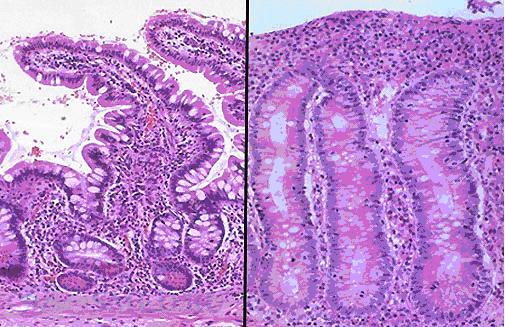

В передней их трети тела расположен присасывательный диск в виде специального углубления. С его помощью лямблии прикрепляются к ворсинкам слизистой оболочки тонкого кишечника. Цитоплазматическая мембрана задней поверхности имеет по краям булавовидные выросты, что также создаёт дополнительную прикрепляющую составляющую.

Жизнедеятельность этих паразитов сопровождаются выделением во внутренние среды организма человека множество токсинов, что просто отравляет его изнутри. Лямблиоз может сопровождаться нарушениями функций печени, кишечника, желчного пузыря, вызвать некоторые расстройства нервной системы, различные аллергические реакции. Прикрепление лямблий к слизистой оболочке кишечника нарушают ее способность всасывать жиры и углеводы, нарушают пристеночное пищеварение, сказывается на ее секреторной, моторной функции. Большие колонии лямблий могут оказывать вредное механическое воздействие и раздражать эпителий кишечника.